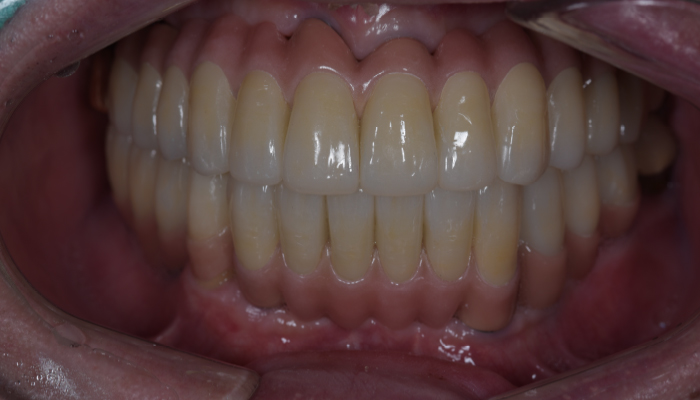

틀니 임플란트 전후 사례

• 식립전

식립후